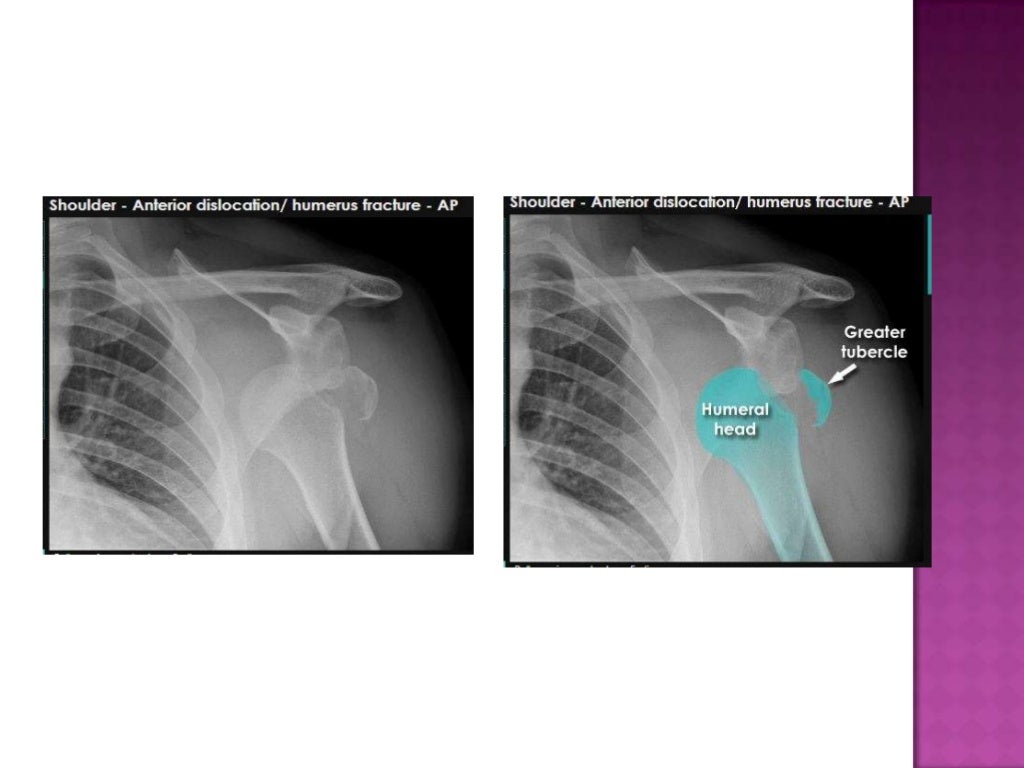

A Anteroposterior shoulder radiograph showing a proximal humeral and Which Joints Are Included On A Humerus Radiograph Distal (refer to elbow joint. Rotate body towards the affected side as needed to bring shoulder and humerus in contact with ir. Rotation of the humeral head. The lateral view of the humerus is part of the humerus series and is usually taken in a standing position. Articular surface of the humeral head covered hemispherically with hyaline cartilage. Proximal (refer. Which Joints Are Included On A Humerus Radiograph.